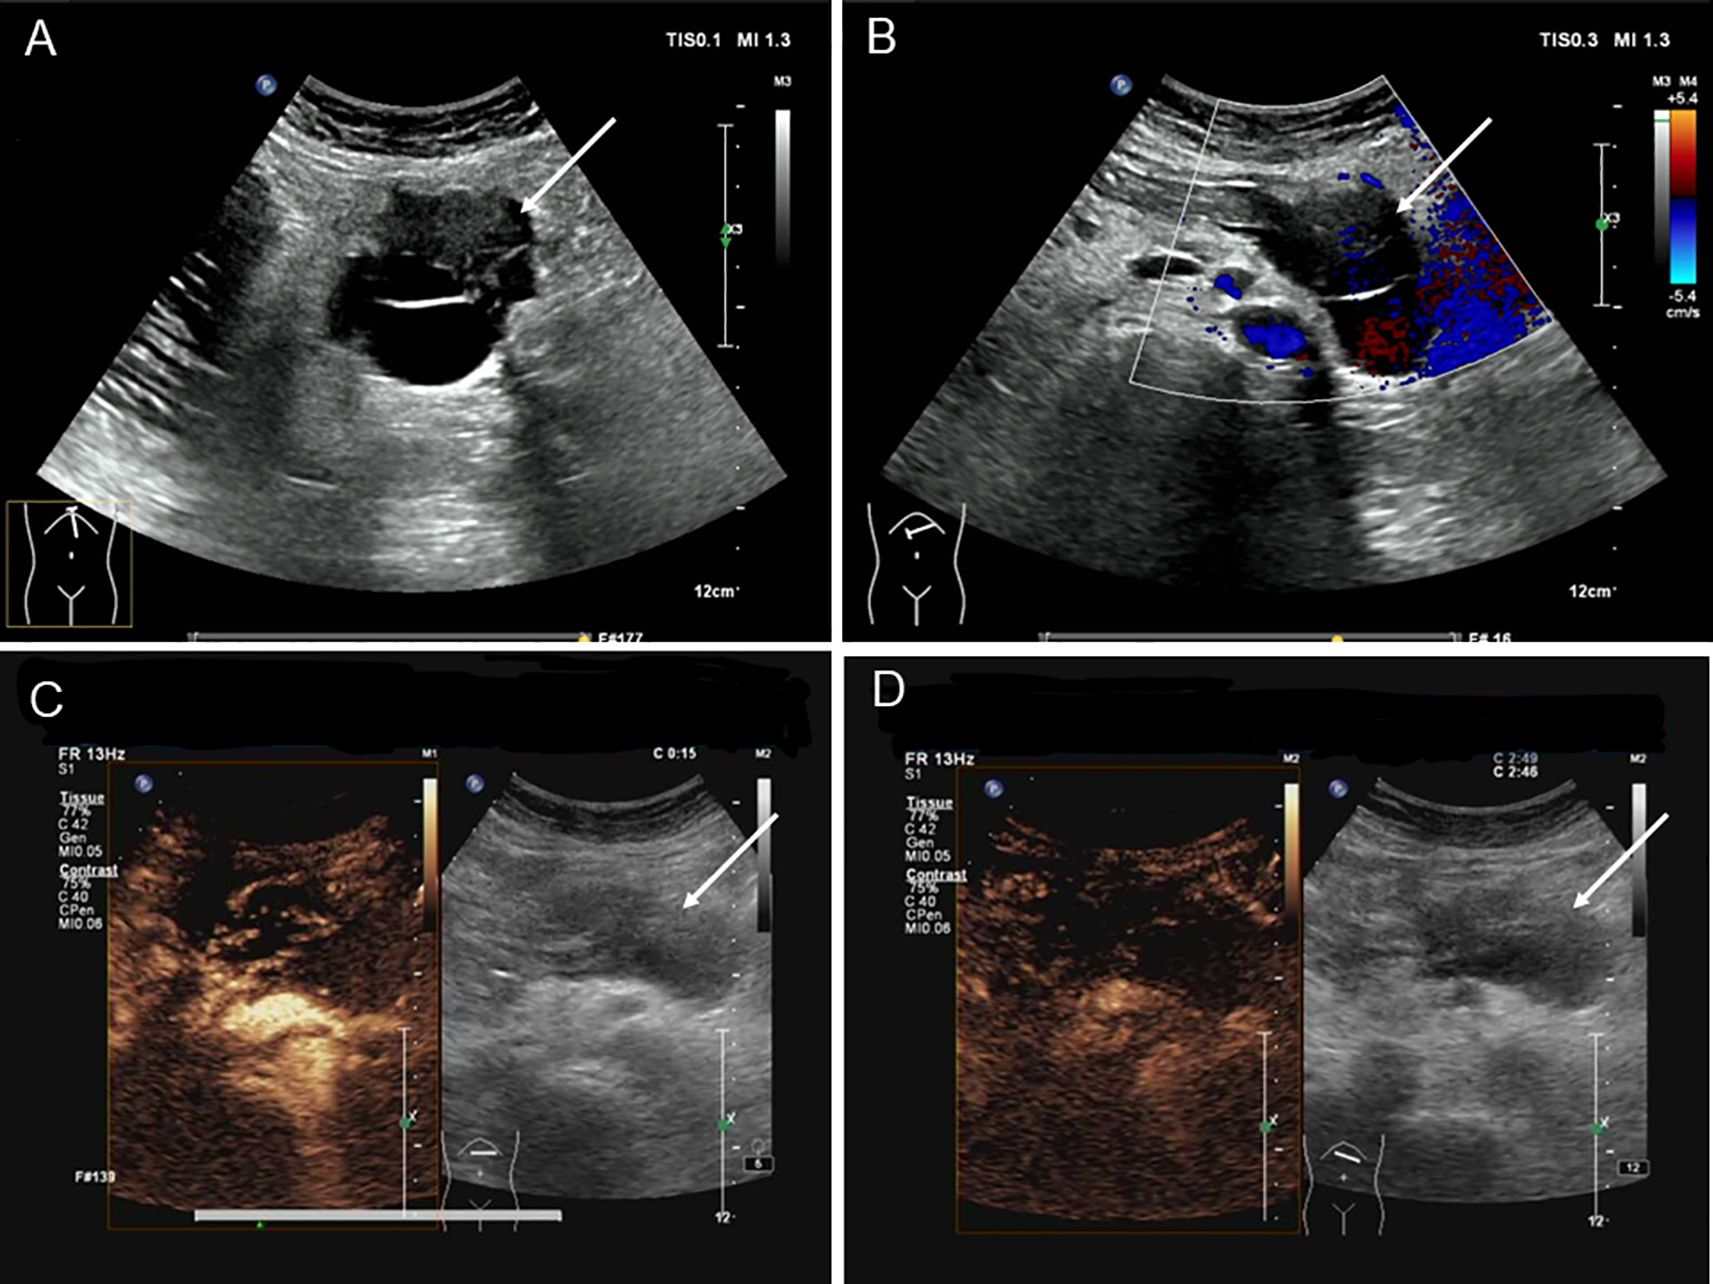

A 39-year-old woman presented with left upper abdominal pain for 20 days and was admitted to the hospital. The pain is persistent and dull in the epigastric region. She described the pain as dull, severe, and non-radiating. The pain was heavier at night than during the day and was related to body position. The bent-knee and bent-hip positions could reduce the pain. It was frequently accompanied by nausea and vomiting, and the vomit was gastric contents and bile. An abdominal CT scan and MRI performed at another hospital had revealed a space-occupying lesion in the pancreas. There was no relevant medical or family history, and the patient had no history of smoking or alcohol consumption. On physical examination, the patient presented with a good general condition and no abnormalities of note. Laboratory tests showed (reference ranges are given in square brackets) the following: glutamyl transferase (72 U/L, reference range 7–32 U/L); lipase (62 U/L, reference range <60 U/L); amylase (31 U/L, reference range 35–135 U/L); and alkaline phosphoric acid (234 U/L, reference range 45–125 U/L). The tumor marker showed no obvious abnormality (CEA, CA199, AFP, and CA125 are normal). The ultrasonography showed a mixed cystic-solid echogenic structure between the body of the pancreas and the posterior wall of the stomach (Figure 1). The mass size was approximately 5.9 cm × 4.1 cm × 3.2 cm with a well-defined margin. The mass was observed to be internally separated by multiple compartments, but there was no obvious relationship with the stomach. A small amount of blood flow signal could be seen. Endoscopic ultrasonography showed a large cystic solid mass in the gastric sinus, posterior to the gastric wall, and at the neck of the pancreas (Figure 2). It was approximately 5.2 × 3.4 cm in size; the border lacked clear boundaries; the solid area was predominant at the wall of the gastric antrum; and the gastric body was dominant behind the cystic region. Multiple septations could be seen within the lesion. The CT plain scan and enhancement showed a mass of flaky cystic-solid mixed-density shadows in the pancreas and gastric hiatus; the lesion was indistinctly distinguished from the gastric wall and the body of the pancreas, and it measured about 6.93 × 3.87 cm. Enhancement scan of the solid portion of the inhomogeneous enhancement, which was considered the possibility of a gastric mesenchymal tumor. MRI showed the lesion with slightly longer T1 and T2 signals, slightly higher signals on DWI, and slightly lower signals on ADC; mild-moderate enhancement; unclear borders; and approximately 3.6 cm × 3.6 cm × 2.8 cm in size; the lesion was poorly demarcated from the neck of the pancreas (Figure 3). To prevent iatrogenic tumor cell dissemination, we also considered the patient’s preference for surgery. Taking all these factors into consideration, we did not perform an endoscopic ultrasound.

Figure 1. Ultrasonography of patient before operation. (A) Ultrasound reveals a cystic-solid mixed echogenic structure between the pancreatic body and the posterior gastric wall, with multiple septa visible within. (B) CDFI showed minimal blood flow signals visible within the tumor. (C) Ultrasound contrast imaging revealed uneven hyperenhancement around the lesion in the early phase of contrast enhancement, with no significant internal enhancement. (D) Ultrasound contrast imaging revealed an uneven low enhancement around the lesion during the late enhancement phase, with well-defined lesion margins.